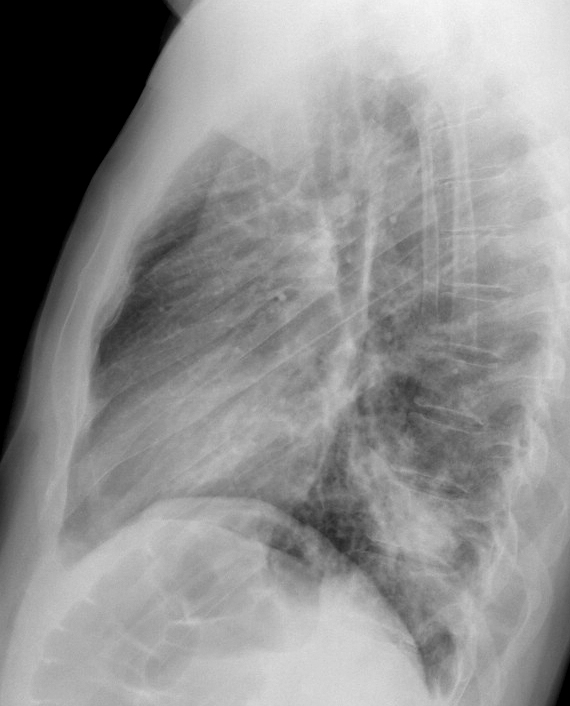

Case 9 RLL brpneum Lat